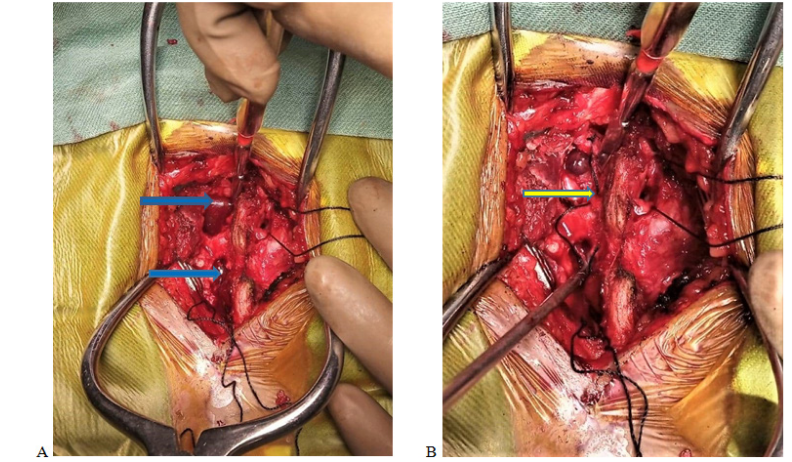

Figure 3 A&B shows epidural venous plexus (A) & type C pattern of venous varicosity pushing nerve root laterally (B), encircling root in cranio-caudal direction & compressing thecal sac. Blue arrow pointing venous varices & yellow arrow pointing nerve root.

Jeong-Hyuk et al has shown that Epidural venous varicosity can be classified into four types based on the relationship between epidural venous varicosity (varices) and nerve structures. Type N is normal anatomical structures with no varices exist. Cases in which varices exist were divided into three types based on the appearance of varices. Type A is conditions in which epidural veins are dilated but located parallel to the nerve root on the lateral side of the nerve root and thus do not compress the nerve root. Type B is conditions in which varices are located on the anterior lateral side of the nerve root to compress the nerve root. Type C is conditions in which varices are encircled around the nerve root and compressing the nerve root.3

As in our case, the preoperative diagnosis was presumed a case of canal stenosis due to centrally herniated disc at L5-S1 level by history, clinical examinations & radiological investigations. Patient was planned for conventional discectomy at L5/S1 level on torso flat prone position with torso on hall frame, abdomen hanging free & hip flexed. After having fenestration done, a plexus of tortuous veins was found in epidural space at L5/S1 level on right side. Nerve root on right side was pushed laterally by varices. Canal was decompressed by punching out ligamentum flavum & discectomy on left side. Postoperatively the radicular pain didn’t subsided satisfactorily hence Resection of varices was planned for second setting after having proper evaluation & investigations of venous varicosity.